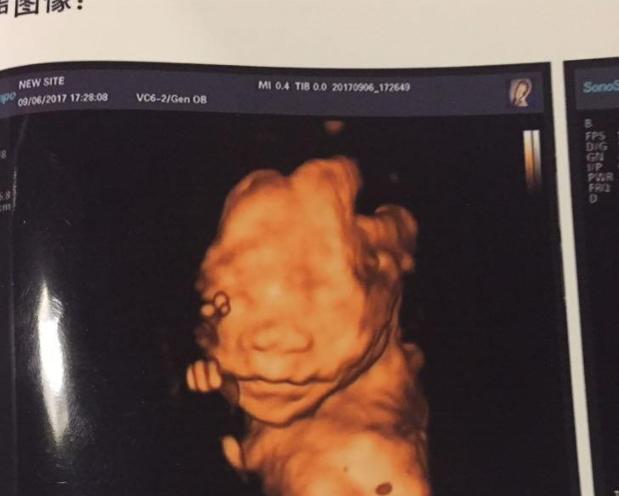

我开了一个水果店,经营的风生水起,老公得到了一个说什么也想不到的位置,1和2都验证了,我们相信3也离我们不远了。于是乎我们选择过完我30生日后,进行2个囊胚的移植。30岁生日3月初,老公给我过了一个非常难忘的生日。定于2019年4月8日进行第二次移植。移植前半个月,每天进行腹部,腰部熏蒸,把身体调整到最好,迎接宝宝的到来。 移植的很顺利,第八天见到粉印,第十天因为没有塞的药了,去医院开药的同时测了个血值138.7,不算低吧也绝对算不上高,因为这次是囊胚,10天的囊胚相当于12天的鲜胚,血值的结果让我想起了上一次,好在10天囊胚的话138.7的结果还能接受,在这个时候*载下**的造造,依然如出一辙的4天后复查血值,提心吊胆的过了4天,复查血值,哇塞,985。成功翻倍而且超级好的血值,医生看了看说,挺好的。不过同时测了下孕酮,大单位3.49ng/ml,这么低?回来查了各种资料,因为一直塞安琪坦,塞药不进血液,不过自身的孕酮百度了半小时,没见有比我低的,医生让我塞药的同时,早晨肌注40mg黄体酮,一周后复查,开心了一周,因为久病半医,血值只要是好的,孕酮嘛,好说!一周后开开心心的去复查,寻思着,一周过去了,985最起码翻10倍,估计得一万二三的血值了,这个时候试纸已经强阳了。一查,7730!7730?怎么才7730,造化弄人,这次给我诊断的医生,就是去年让我停药的大夫,她一皱眉头,说,太低了。翻的不好,毕竟是囊胚,前期本身就低,移植都21天了,起码也得个一万了,再继续用药看看吧,看来是一批出来的胚胎,确实不太好。。。不过B超已经看到卵黄囊了,确认宫内有孕囊。。。。。。。 老公很乐观,说,如果严格意义来说,985隔天1.66倍的话也勉强及格。回来各种百度各种查资料,情况算不上太差吧但绝对算不上好。继续让我一周后复查。 不知是巧合还是注定,因为打听到港黄可以代替肌注黄体酮,认识了“大雁向北飞”这个至关重要的姐姐,她转港黄,也是山东人,我把我的情况跟她简单说了说,她说。我建议你去咨询一下山东潍坊人民医院的付锦华,她是全国有名的保胎医生,我当晚就在好大夫上咨询了她,巧了她立马给我回话,告诉我情况不算好不算坏,希望很大,让我先第一时间注射一针艾泽,一针瑞白,然后去潍坊面诊她。一夜无眠,毕竟潍坊虽说是同省,距离及陌生感让我不知所措,但还是搜了付锦华的qq群,认识了“花儿对我笑”天津的姐姐,她给我详细的分析了我的情况劝我火速来医,病急乱投医的我抛去之前的怀疑,毅然决然的走上了潍坊问诊之路。 来到潍坊初诊已经是移植第25天了,初诊费花了8000多元,抽了我24管血,化验单一米多长,胎停全套的检查及保胎常规化验,我才知道,齐鲁医院专业于如何进行辅助生殖及移植,而真正的保胎及习惯性流产治疗他们并不专业,既来之则安之。当天的血值17300,从21天的7730到25天的17300,过万后日均3000的及格线也没踏入,心如死灰吧算是,说实话这个时候已经有点放弃的感觉了。付主任鼓励我,还有戏,别放弃,明天拍个B超看看。找到日租房准备长期奋战。第二天一查,有胎心胎芽了已经,胎芽0.3cm,我的天!这就有胎心了?我的天,当时泪如雨下。我的宝宝来了!激动的告诉付主任,付主任说,是不错但是呢,一万多的血值过早的见胎心,看看后期能挺起来不,一般最早三万左右见胎心,不排除别的情况,如果血值能翻的起来,就有希望,强大的内心告诉我,我相信宝宝,然后再查血值,17300两天后21998,依然没有达标日均3000,我每天都摸着肚子告诉宝宝说一定加油!期间的用药包括肝素,达芙通,肌苷片,补佳乐,VD,纷乐,泼尼松等等,血值隔天从21998一路32000,一路越来越好,详情见图,老公给我做了个表,详细的记录所有的每一次检查的指标,再一次哭着感谢老公,每一次的血值,孕酮,雌二醇,泌乳素,子宫动脉,nk,ca125,免疫,肿瘤因子,白介素等所有指标一一记录。终于在血值达到8万隔天10万的时候迎来了二超,各项指标日趋完美,我知道我的宝贝在努力,我知道我一定可以!9周2天的B超跟孕周大小一天不差完美吻合,也告别了再纠结hcg的日子,只需关注孕酮和雌二醇就可以了。在我最孤独无助,彷徨的时候,“花儿对我笑”姐姐给我科普了所有的指标知识,让我从一个小白痴,变成了半个保胎专家,而不幸的是,她不知原因的出血迎来了再一次的生化,心灰意冷的回家抚平心情了,我哭了好久,为她心疼,也为自己担心以后无人陪我。她告诉我,她不想再接触和影响我了,保胎的路上就让我自己前行吧,我哭的像个*逼傻**,她告诉我“别担心,莫愁前路无知己”,调整了两天,昂首挺胸继续前行。打算从潍坊回家过个周末,已经出来一个月了。主任告诉我,这几天再查个雌二醇,我没当回事,回家在县医院查了个雌二醇和孕酮,我的妈,雌二醇三天从5200掉到2600,马上通知主任,主任告诉我,抓紧去B超,不太好,降太多,在县医院挂急诊做了个b超,一看,宝宝依然很好,告诉主任,主任埋怨我为何不告诉她在不同医院查的雌二醇!不同医院没有可比性!虚惊一场,在造造上发帖,认识了一个奇怪的可爱的女人,在这里称她为Alice,她笑我玻璃心,然后把我拉进一个对我来说最最最重要的微信群,同时在付主任那里保胎的同胞另一个跟我同病相怜的另一个奇怪的可爱的姐妹q星,一起拉进了群,也是她们给了我最大的鼓励,感谢你们(二宝妈,冉妈,娴娴,小白等等所有那些我没有提到的那些姐们们),一直到付主任告诉我nt完美通过你可以顺利毕业回去待产了! 就这样,浑浑噩噩的来到了16周,医院得知我老公染色体多态性的问题让我羊穿,后因为肝素不能停改为无创,无创顺利通过,宝贝偏大5天。大排畸秒过,四维去了三次医院一共拍了十几次,终于在昨天顺利给正脸了!激动!小胖墩已经偏大一周了!